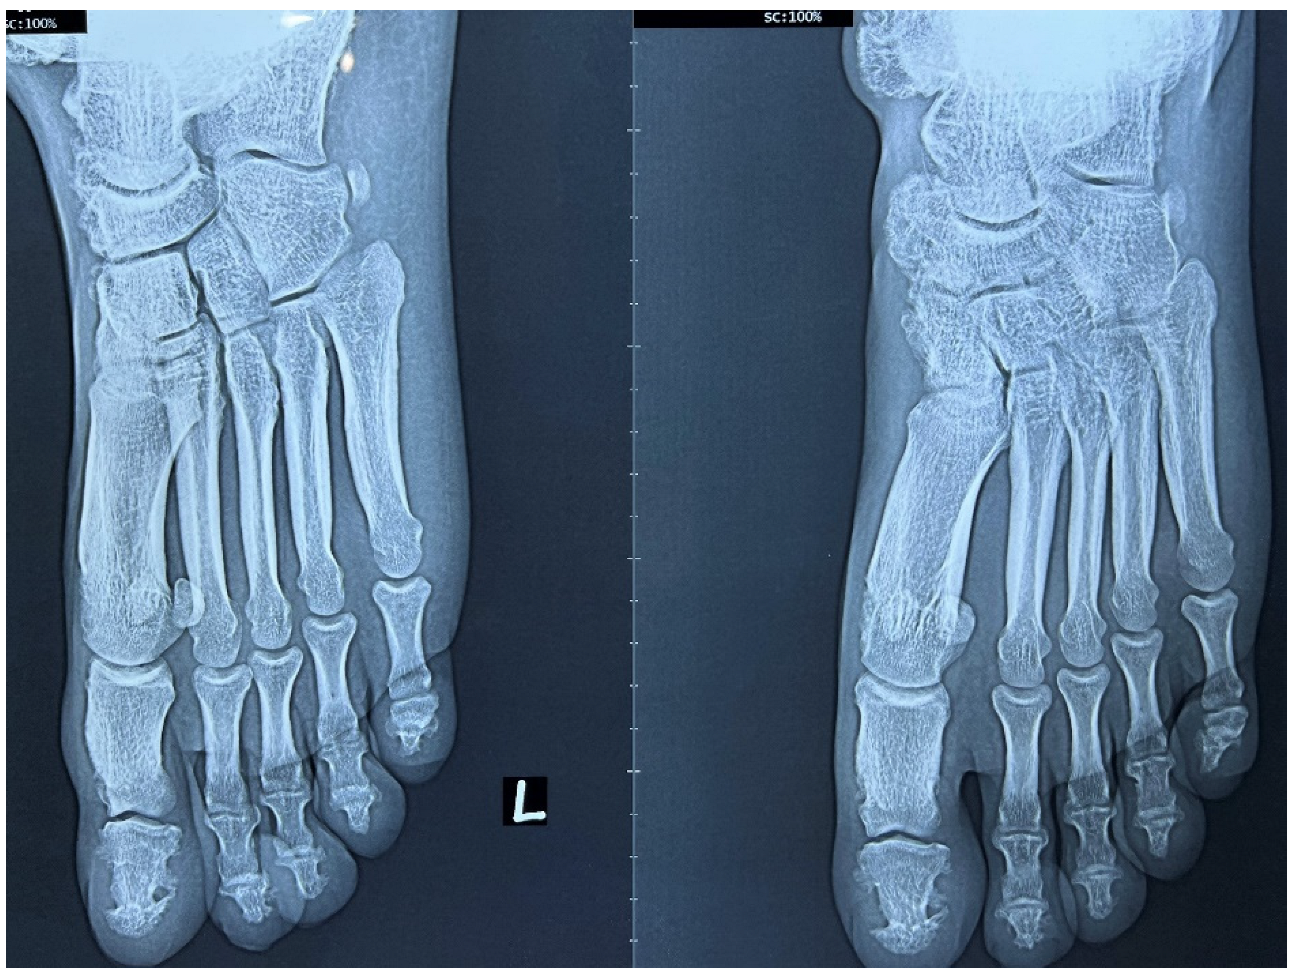

2. Case Report